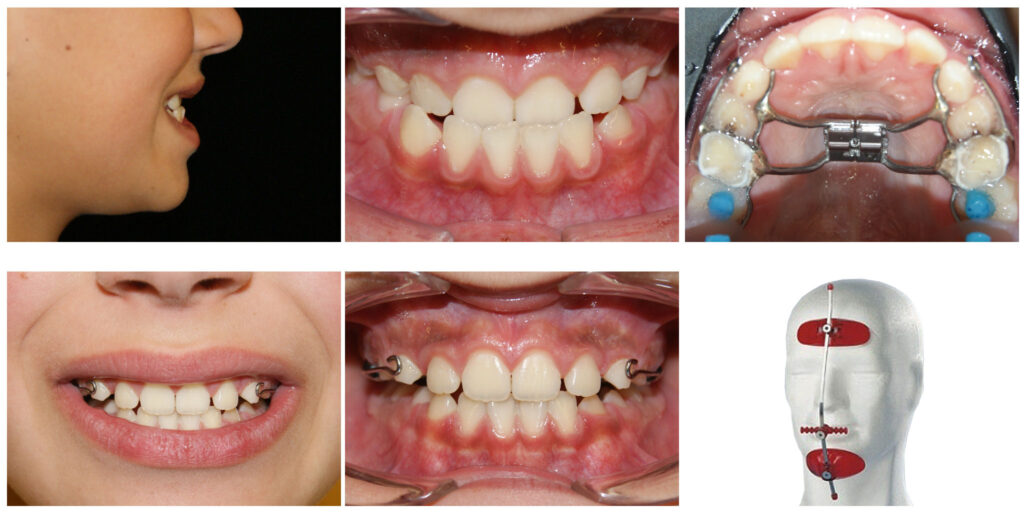

Corectarea muscaturii inverse cu forte extraorale – masca Delaire și disjunctor maxilar Alegem aparatul potrivit la vârsta potrivită

Corectarea muscaturii inverse cu forte extraorale – masca Delaire și disjunctor maxilar. Câteva luni pentru rezultate de care copilul se bucură întreaga viată